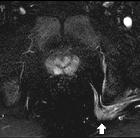

Neurofibromas are benign peripheral nerve sheath tumors usually solitary and sporadic, however, there is a strong association with neurofibromatosis type 1 (NF1). These tumors present as a well-defined hypodense mass with minimal or no contrast enhancement on CT. On MRI, they usually are T1 hypointense and T2 hyperintense with heterogeneous contrast enhancement.

Radiographic features

General imaging features of neurofibromas:

MRI

- T1: hypointense

- T2

- hyperintense

- target sign

- a hyperintense rim and central area of a low signal may be seen

- this is thought to be due to a dense central area of collagenous stroma

- although this sign is highly suggestive of neurofibroma, it is occasionally also seen in schwannomas and malignant peripheral nerve sheath tumors

- fascicular sign

- T1 C+ (Gd): heterogeneous enhancement